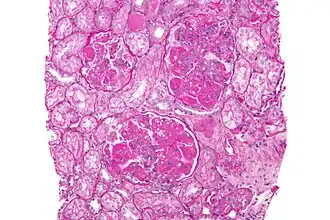

Se encuentra afectación renal clínica aproximadamente un 50 % de los pacientes; sin embargo, la mayoría del resto de pacientes tiene enfermedad subclínica que se puede observar si se realiza una biopsia renal. La afectación renal habitualmente ocurre en los primeros años de la enfermedad y debería ser detectada de modo temprano mediante análisis periódicos de orina y de la función renal.[60] Una hematuria o proteinuria indoloras suelen ser el único hallazgo inicial renal. La afectación renal es una de las principales causas de morbilidad y mortalidad en LES; aunque, debido al reconocimiento y tratamiento precoz, las últimas fases de enfermedad renal crónica se observan en menos del 5 % de los pacientes. Pueden presentarse diversas formas de glomerulonefritis, siendo la biopsia renal necesaria para determinar el tipo y la extensión de la afectación renal.[60]

En 2004 se desarrolló un sistema de clasificación de la nefritis lúpica, denominado clasificación ISN (International Society of Nephrology) determinada por la biopsia renal.[61]

- Nefritis lúpica con cambios mínimos mesangiales (clase I).

- Nefritis lúpica con proliferación mesangial (clase II).

- Nefritis lúpica focal (clase III).

- Nefritis lúpica difusa (clase IV).

- Nefritis lúpica membranosa (clase V).

- Nefritis lúpica esclerosante evolucionada (clase VI).

Además de las lesiones glomerulares hay otras formas de enfermedad renal en el LES, incluyendo nefritis tubulointersticial, enfermedad vascular, microangiopatía trombótica y lupus podocitopatía.[62]